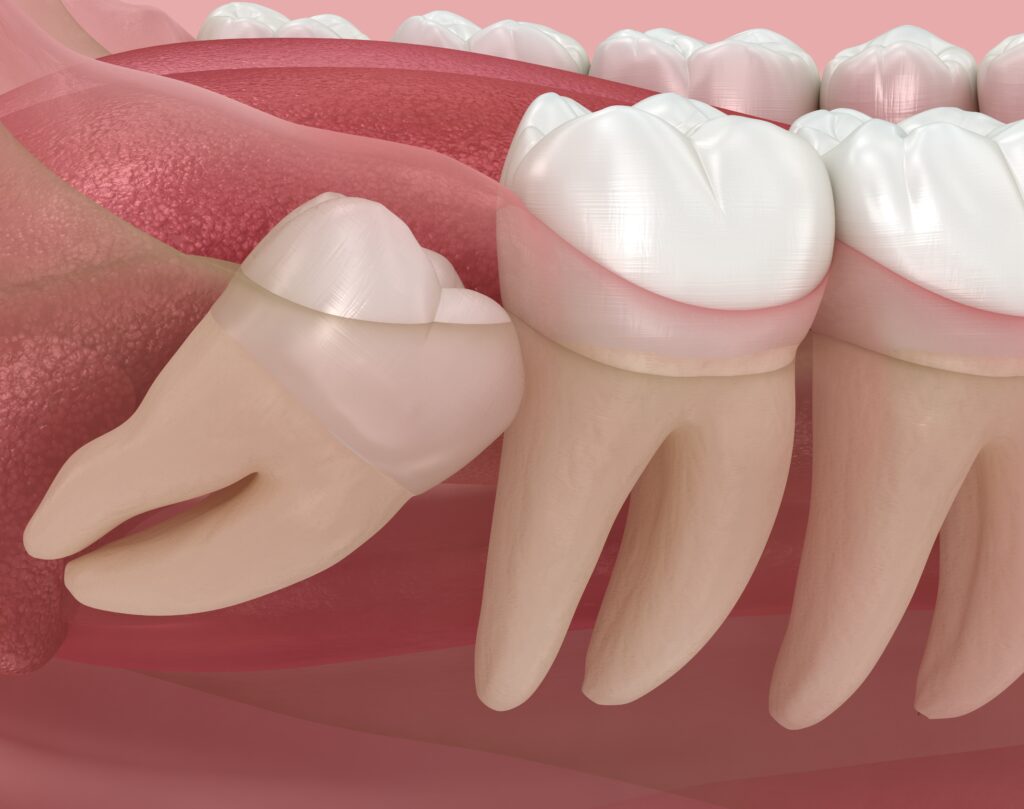

“매복사랑니란?”

현대인들은 인류의 진화 과정을 거치며

턱뼈의 크기가 점차 작아지는 경향을 보이고 있습니다.

이로 인해 가장 마지막에 나오는 사랑니가

제대로 자리 잡을 공간이 부족해지면서

잇몸 속에 파묻히거나 비스듬하게 누워서

자라나는 부정적인 양상을 띠게 됩니다.

잇몸 속에 완전히 또는 부분적으로

숨어 있는 상태를 매복이라고 표현합니다.

사랑니가 바르게 나오지 못하고

매복되어 있으면 치아와 잇몸 사이에

미세한 틈이 생기기 쉽습니다.

이 틈으로 음식물 찌꺼기가 들어가면

일반적인 칫솔질로는 제거하기가 매우 어렵습니다.

결국 이곳에 박테리아가 번식하면서

잇몸이 붓고 피가 나는 염증 반응이 일어나는데

이를 치관주위염이라고 부릅니다.

또한 사랑니가 바로 앞의 소중한 어금니를

지속적으로 밀어내면서 치열을 어긋나게 하거나

앞쪽 치아의 뿌리 부분을 손상시켜

함께 충치를 유발하는 일도 빈번합니다.